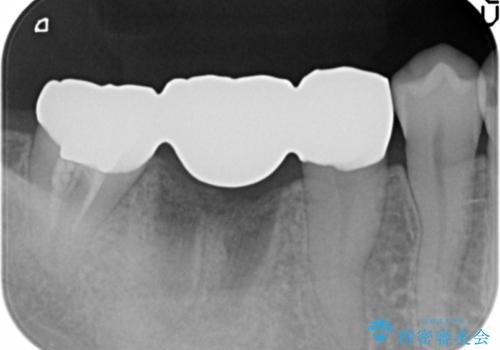

抜歯後は、奥の銀歯も一緒に白くできるブリッジ治療を希望されました。

- 33万円(仮歯・ジルコニアクラウン×3)費用は治療当時の料金となります

ブリッジ治療で比較的早期に咬合機能を回復することができました。